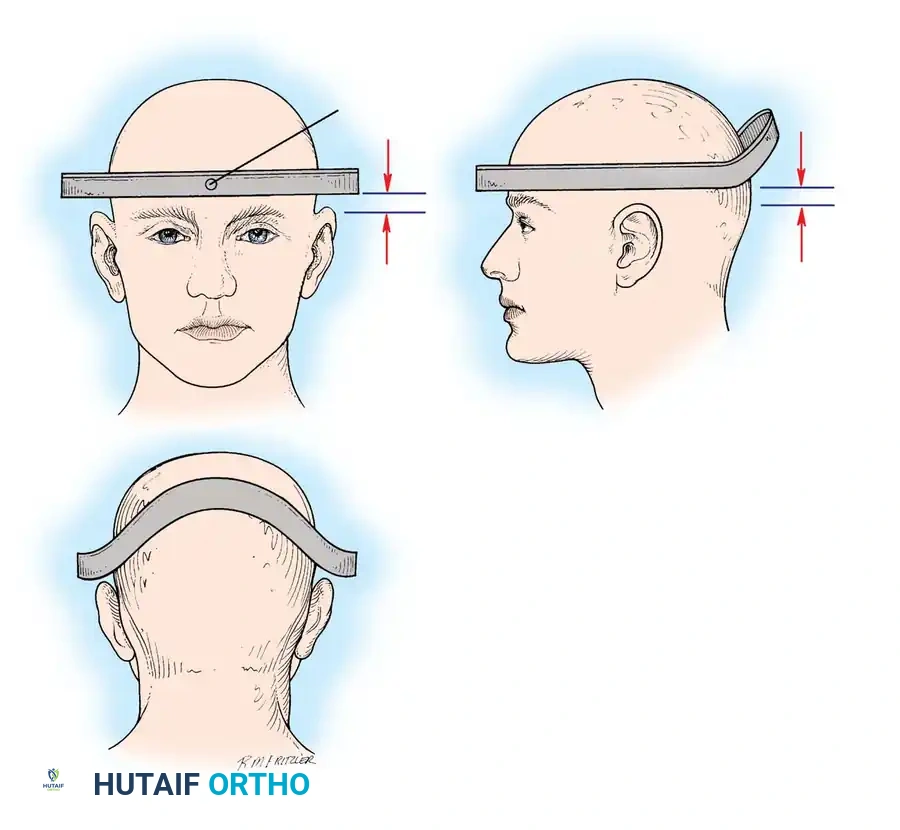

🔪 Surgical Technique 35-1: The Stretch Test Protocol

- Preparation: Apply traction through secured cranial skeletal traction (Gardner-Wells tongs). A head halter is inadequate for the weights required and risks skin necrosis. Place a rolled towel under the patient’s neck to maintain a neutral lordotic contour.

- Baseline Imaging: Place the radiographic film/detector as close to the neck as possible. Position the X-ray tube 72 inches away to minimize magnification, and obtain a baseline lateral radiograph.

- Incremental Loading: Begin with 10 lb of traction. Increase the weight in 5-lb increments.

- Monitoring: After each 5-lb addition, perform a strict neurological examination and obtain a repeat lateral radiograph.

- Viscoelastic Creep: Allow at least 5 minutes between incremental weight applications to account for the viscoelastic creep of the disrupted ligamentous structures.

- Endpoints: Continue until one of the following endpoints is reached:

- One-third of the patient's body weight is applied.

- A maximum of 65 lb is reached.

- Positive Test (STOP IMMEDIATELY): Any neurological deterioration occurs, interspace separation exceeds 1.7 mm, or the angular difference between the prestretched and loaded condition exceeds 7.5 degrees.

After initial ATLS medical stabilization, spinal alignment is typically attempted via closed skeletal traction using spring-loaded Gardner-Wells tongs or a halo ring.